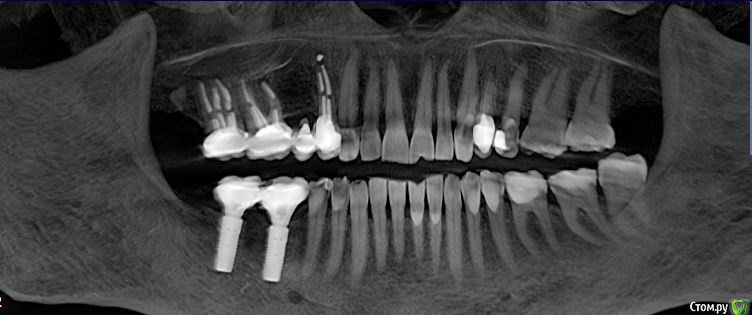

favirit Опубликовано 26 февраля, 2019 Поделиться Опубликовано 26 февраля, 2019 Добрый день! Мне 65 лет. Пришла к врачу по поводу небольшой рецессии десны у имплантов. Импланты стоят 5 лет. Сделали компьютерную томограмму. Врач в ужасе. Увидел на верхней челюсти переломы корней у трех зубов под мостом. Предлагает снять мост, удалить 3 зуба, у которых сломаны корни, и установить 2 импланта. У меня никаких жалоб нет. На десне образований нет, подвижности зубов нет, боли нетПрошу посмотреть кадр КТ.При необходимости выложу КТ.Спасибо. 1 Ссылка на комментарий

kramer Опубликовано 26 февраля, 2019 Поделиться Опубликовано 26 февраля, 2019 Разумеется, никакого перелома там нет. 4 Ссылка на комментарий

favirit Опубликовано 27 февраля, 2019 Автор Поделиться Опубликовано 27 февраля, 2019 Разумеется, никакого перелома там нет. Тогда почему такой вид у запломбированных каналов? Ссылка на комментарий

red_butler Опубликовано 27 февраля, 2019 Поделиться Опубликовано 27 февраля, 2019 Тогда почему такой вид у запломбированных каналов? зубы восстановлены корневыми вкладками Ссылка на комментарий